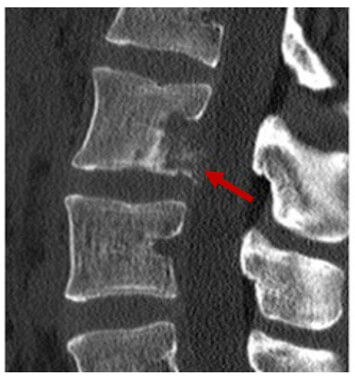

Targeting

Targeting is a magnification technique done through reformatting. The reformatting process reconstructs image data in smaller pixel sizes to permit magnification with less distortion. This is done for areas where fine detail is needed, such as in the inner ear. Here you can see the magnified fracture in the lumbar spine.